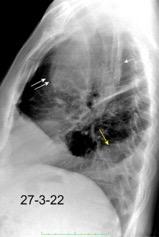

Marzo 2014: Perforación longitudinal distal secundaria a episodio de vómito (síndrome de Boerhaave). Derrame pleural izdo. que evoluciona a empiema.

Wang C-T et al. Tension hydropneumothorax in a Boerhaave syndrome patient: A case report . World J Emerg Med, 2021. Katabathina V et al. Nonvascular, nontraumatic mediastinal emergencies in adults:a comprehensive review of imaging findings. Radiographics. 2011.